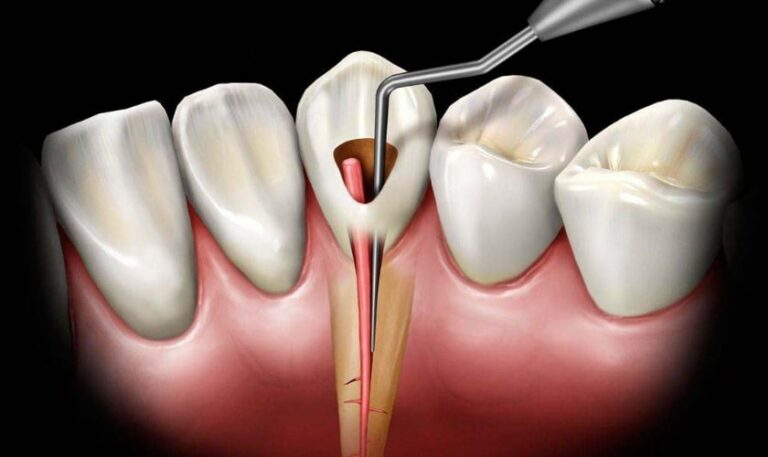

- CBCT-Guided Root Canal Procedure

Your comfort is our top priority. After the tooth is completely numbed, Dr. Xia utilizes CBCT to obtain detailed three-dimensional imagery of your tooth’s internal anatomy. This advanced imaging technology provides exceptional clarity, allowing for a thorough cleaning and disinfection of even the most intricate root canal spaces. By enhancing visualization, CBCT significantly improves the accuracy and success of the procedure.

Following the removal of the infected pulp, the canal is meticulously shaped, disinfected, and sealed with a biocompatible material to prevent future reinfection.